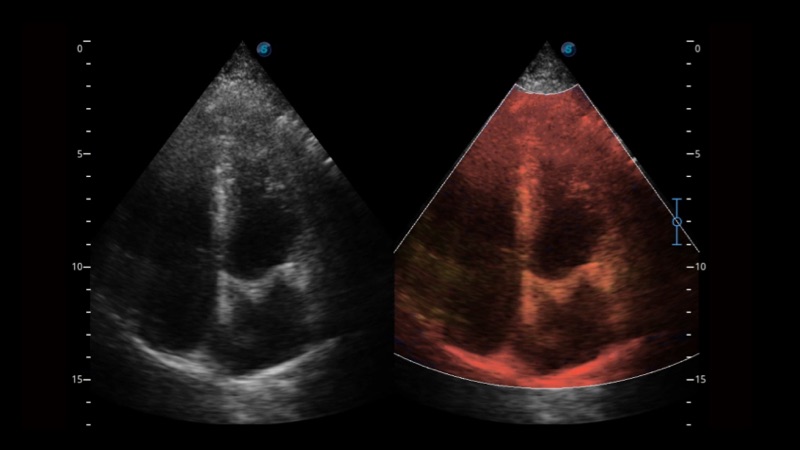

组织多普勒

组织多普勒成像功能,可提供心肌运动速度和其他临床信息,使临床医生能够分析和比较患者心脏不同部位的运动。

临床图像